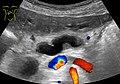

Ultrasonography of a dilated pancreatic duct (in this case 9mm) due to pancreatic cancer.